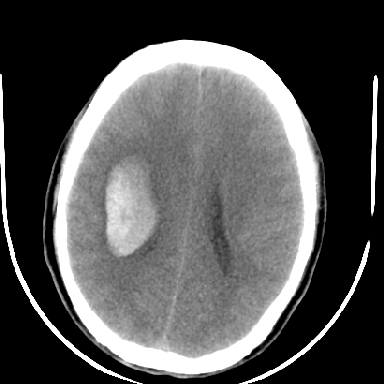

标题: CT6056:脑出血(血管畸形?) [打印本页]

标题: CT6056:脑出血(血管畸形?)

m 40突发头痛左侧偏瘫3小时

支持右侧基底节脑出血

右侧基底节区脑出血.

支持右侧基底节区(主要为外囊区)原发性脑出血。

另附部分资料:“血液溢出血管外形成血肿,其内含有大量血红蛋白、血浆白蛋白,球蛋白,因这些蛋白对x线的吸收系数高于脑质,故ct呈现高密度阴影,ct值达40~90h,最初高密度灶呈非均匀一致性,中心密度更高,新鲜出血灶边缘不清。基底节区血肿多为“肾”型,内侧凹陷,外侧膨隆,因外侧裂阻力较小,故向外凸,其它部位血肿多呈尖圆形或不规则形”

术中抽出40ml陈旧血液,血肿底部似见一条索血管影